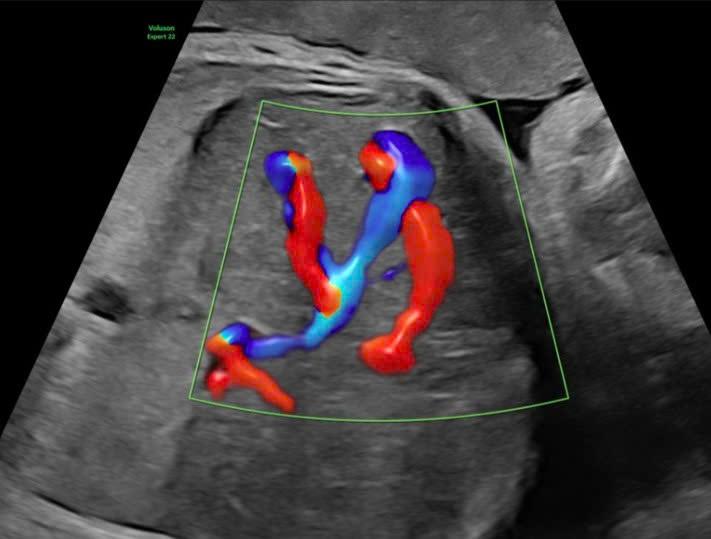

Ultrasound image showing the abnormal hepatic vascular malformation. *Hong Ngoc General Hospital* |

Each examination included a comprehensive fetal assessment via specialized Doppler ultrasound to evaluate blood flow within the hepatic vascular system, measuring the velocity and direction of blood through the abnormal shunt. Doctors also closely monitored hemodynamic indicators, such as cardiac output, signs of circulatory overload, and the risk of fetal heart failure.